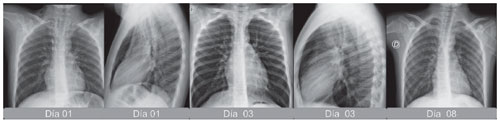

Posteriormente, se le realizaron controles radiográficos durante la primera semana de estancia con disminución del neumomediastino y enfisema (Ver Figura 3). En el día primero se observaron imágenes radiolúcidas, que separaban la silueta cardiaca de una línea radiopaca que corresponde al pericardio separado por la presencia de aire tanto en la proyección AP como lateral. En los días siguientes desaparecieron gradualmente los hallazgos.